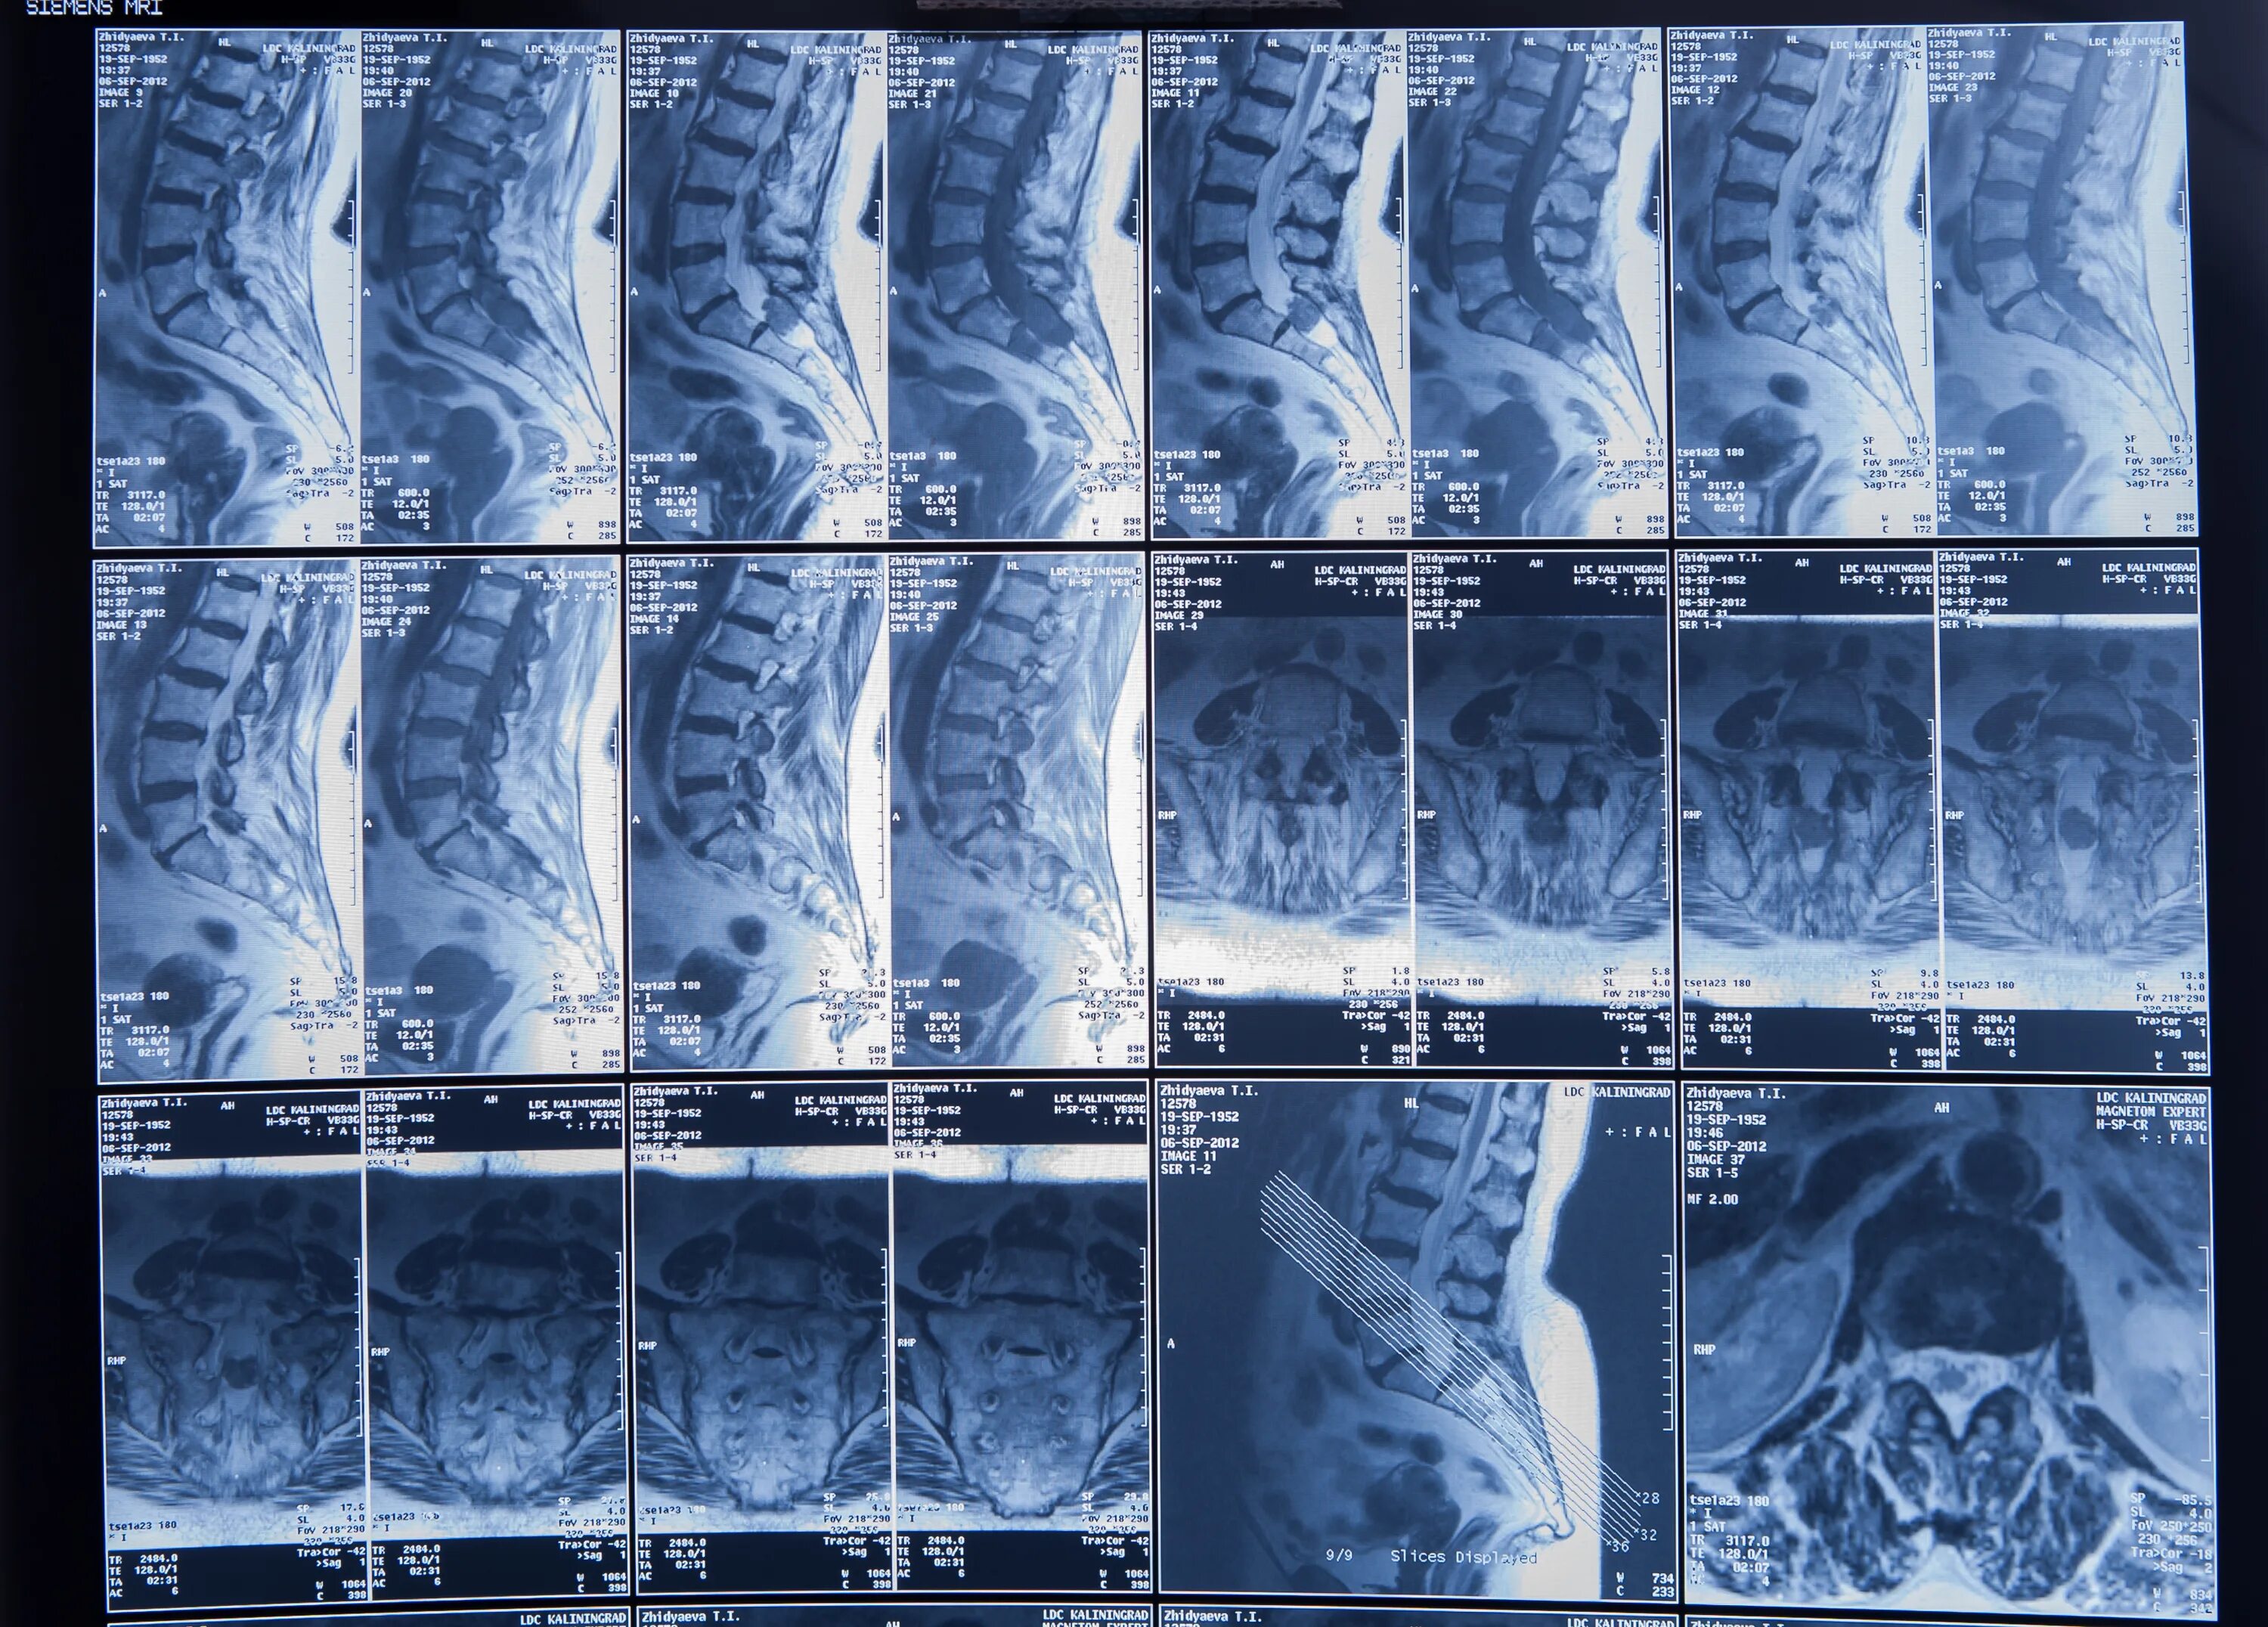

Чем отличается кт от мрт поясничного отдела